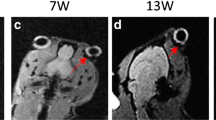

The data of excised sclera in vitro suggest large effective pore size for transscleral transport and negligible pore charge effects upon the permeation of the ionic permeants. The permeability coefficients of Mn2+ and MnEDTA2- across the sclera in vitro were 3.6 × 10-5 cm/s and 2.4 × 10-5 cm/s, respectively. Although relatively high sclera permeability was observed in vitro, subconjunctival injections in vivo did not provide significant penetration of Mn2+ and MnEDTA2- into the globe; permeant concentrations in the eye were below the detection limit, which corresponds to less than 0.05% of the concentration of the injection solution (e.g., less than 0.02 mM when 40 mM injection solution was used). The volume of the subconjunctival pocket and the concentration of the permeants in the pocket were observed to decrease with time after the injection, and this could contribute to the lower than expected subconjunctival absorption in vivo. Different from the results in vivo, experiments with rabbits postmortem show significant penetration of Mn2+ and MnEDTA2- into the globe with the permeants primarily delivered into the anterior segment of the eye. This difference suggests blood vasculature clearance as a main barrier for passive transscleral transport. The data also show that the pars plicata/pars plana is the least resistance pathway for passive transscleral drug delivery of the polar permeants, and there are indications of the presence of another barrier, possibly the retinal epithelium and/or Bruch’s membrane, at the back of the eye.